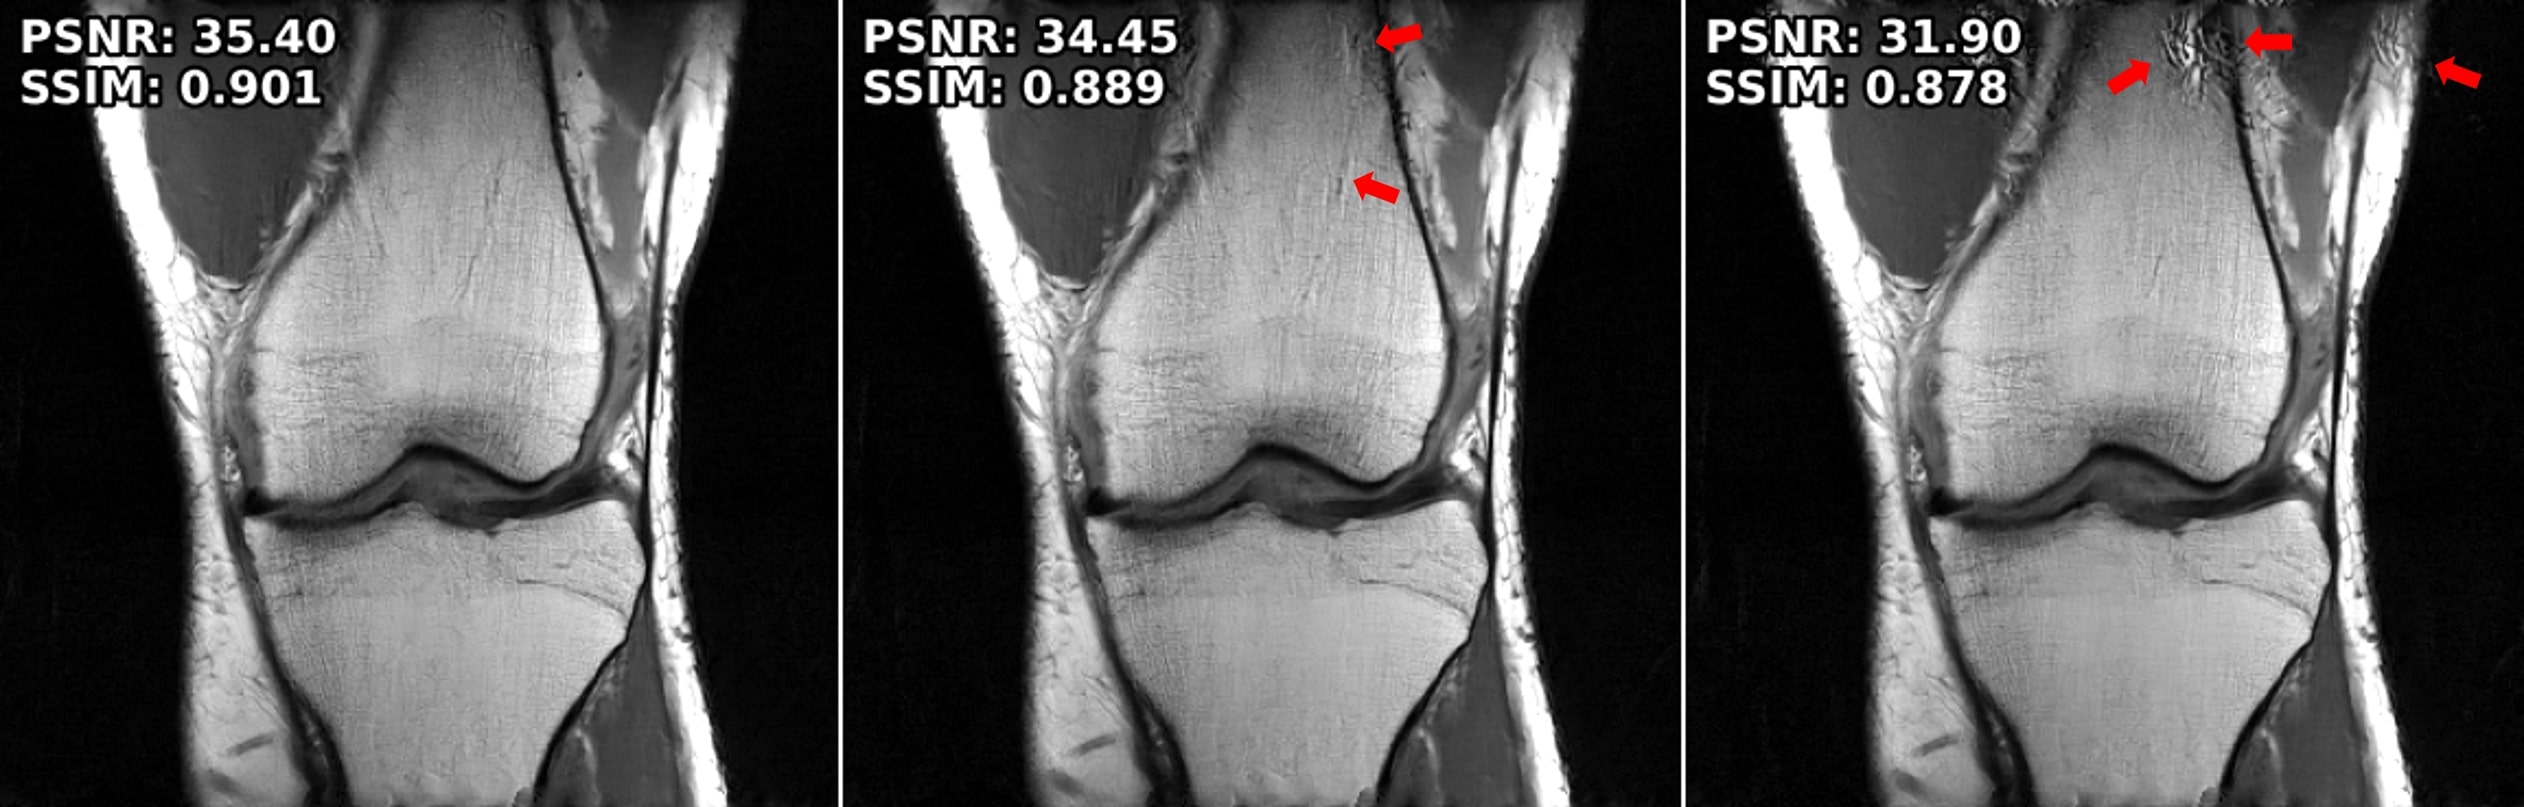

Figure 4: Performance across different attack strengths. Both Adversarial Training and the proposed method applied to MoDL work across different perturbation levels, with the proposed method leading to fewer visual artifacts in both.

Performance Across Error Strengths. We next test the performance of the methods across different error strengths, ϵ{0.01,0.02}italic-ϵ0.010.02\epsilon\in\{0.01,0.02\}italic_ϵ ∈ { 0.01 , 0.02 }. Fig 4 shows the results for the robust methods trained with ϵ=0.01italic-ϵ0.01\epsilon=0.01italic_ϵ = 0.01 and the proposed method for both attack strengths. The results show SMUG fails to preserve the performance on both setups, while Adversarial Training and the proposed method have an acceptable mitigation on each attack strength. Adversarial Training suffers from blurriness and visual artifacts, while the proposed method retains sharpness and details. Both methods show degraded PSNR/SSIM as a result of the stronger attack. Further quantitative results are provided in SuppMat.